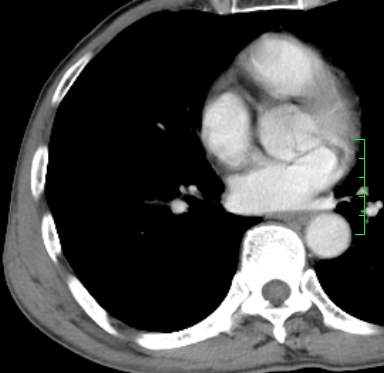

m,73y。膝关节疼痛伴双下肢水肿。入院常规胸片发现结节灶。增强为静脉期。

浅分叶、棘突,考虑右下肺周围型肺癌

考虑周围型肺癌  ,双上肺结核。

肿块周围可见局限性气肿,考虑肺癌可能性大。双肺上叶继发型肺结核。

指套征,强化明显,近侧肺组织局限性肺气肿,考虑支气管类癌,慢支、肺气肿、双上陈旧性tb、冠脉钙化。

鉴别:先天性支气管闭锁,变态反应性支气管肺曲霉菌病,肺癌,支气管囊肿,支扩黏液嵌塞。

1)考虑右肺下叶周围型肺癌。2)右肺上叶及左肺感染性病变(结核可能)。3)肺气肿。4)冠状动脉钙化。